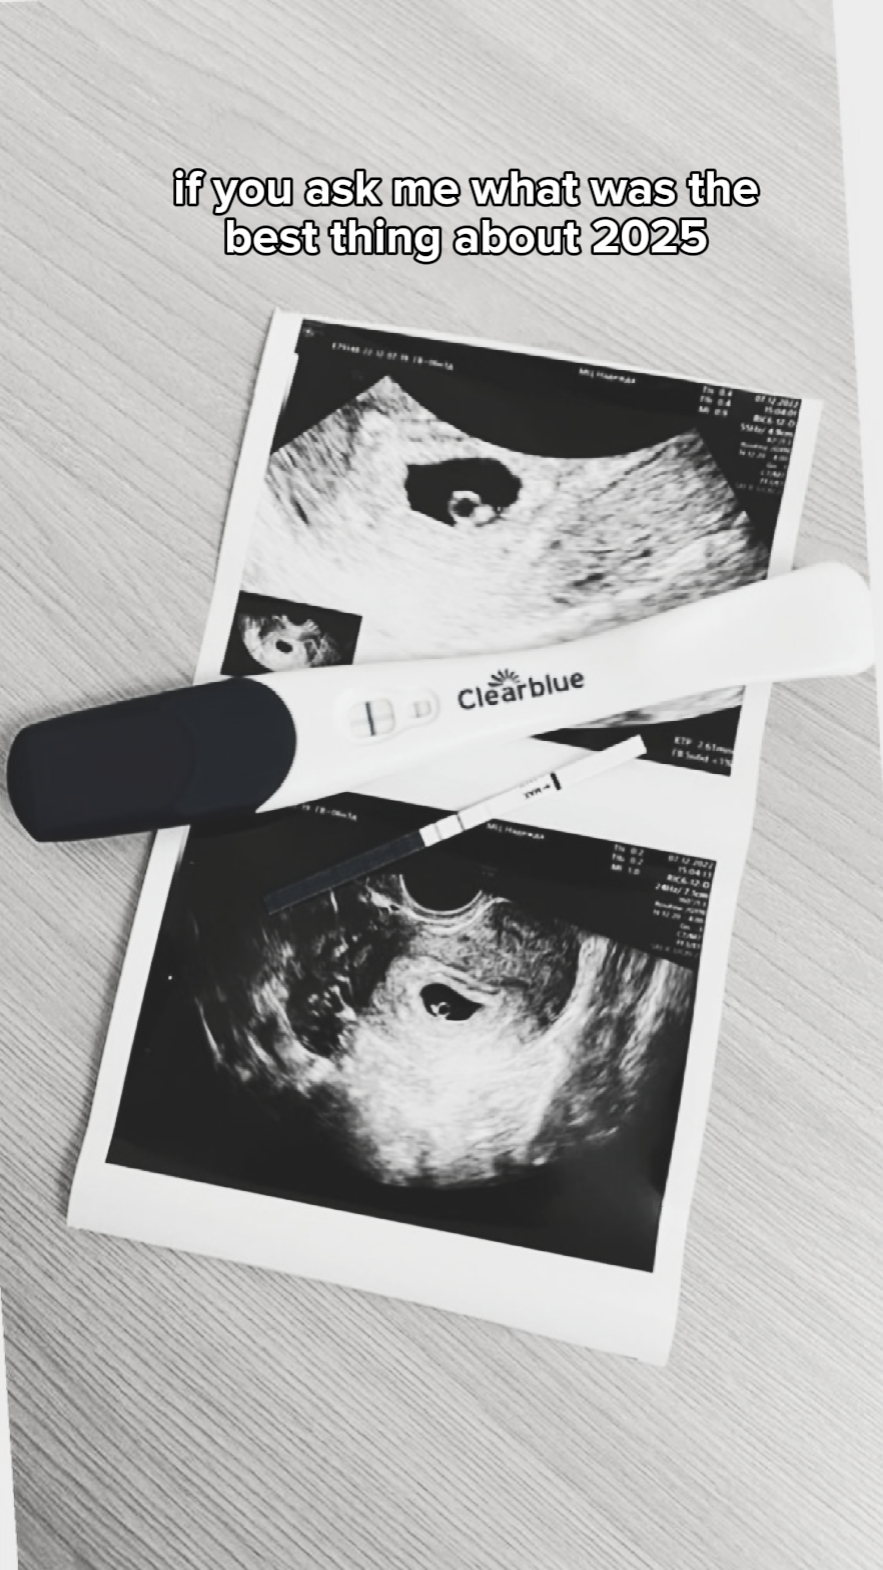

Retrospectiva De 2025 Com Minha Esposa

Reviva os melhores momentos de 2025 com a Pippit! Se você está pensando em criar uma retrospectiva especial com a sua esposa, essas lembranças merecem ser eternizadas de forma elegante e inesquecível. As ferramentas de edição de vídeo da Pippit oferecem tudo o que você precisa para transformar momentos únicos em uma narrativa visual emocionante e repleta de memórias.